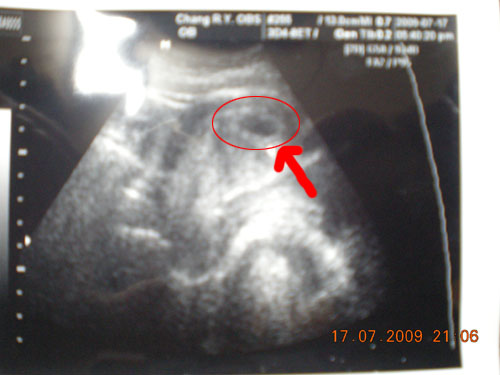

2009.07.17

首次發現懷孕~只有些許徵兆~胎兒還沒有成型~只是個胚胎= =!!